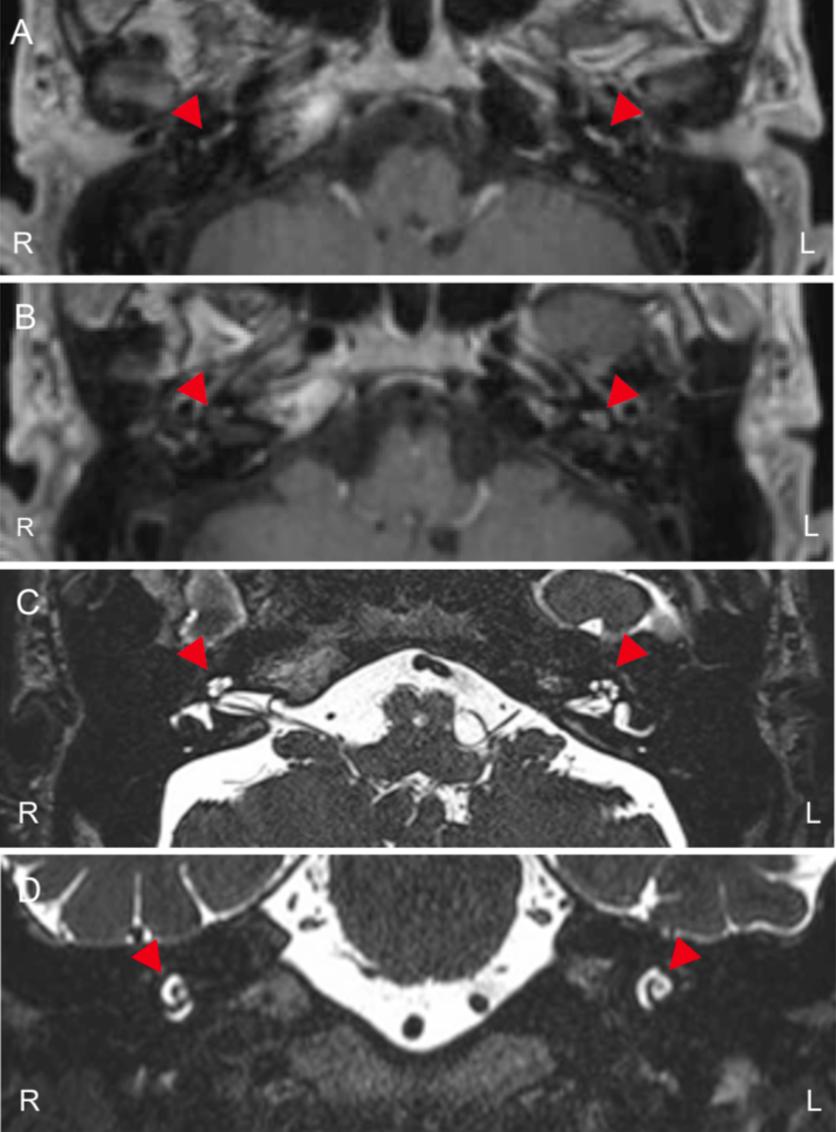

用化学发光酶免疫分析法测定抗蛋白酶3(PR3)和髓过氧化物酶(MPO)的ANCA水平,分别上升到31.2 U/ml和159 U/ml,两个参考范围均小于3.5 U/ml(表1)。同时,还检测到高效价的环瓜氨酸肽(CCP)和谷氨酸脱羧酶(GAD)抗体。然而,这个病人没有其他器官受累,例如小血管炎或类风湿关节炎。他肾功能无明显异常,无蛋白尿和尿潜血(表1和表2),计算机断层扫描显示无副鼻窦和肺部受累(图3,A和B)。然而,核磁共振图像显示两个耳蜗的T1加权图像存在对比度效应(图4,A和B),尽管T2加权图像中耳蜗的结构似乎保持不变(图4,C和D)。